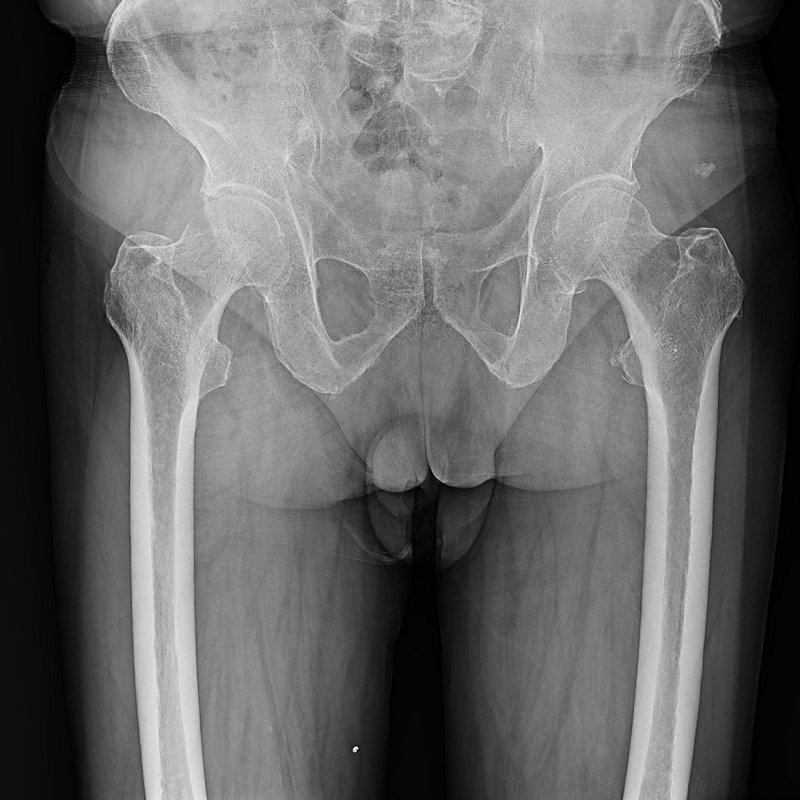

● 低位攝影

球管及胸片架可大范圍縱向移動(dòng),平板探測(cè)器中心最低離地35cm,輕松滿足膝關(guān)節(jié)、踝關(guān)節(jié)等低位攝影的要求。